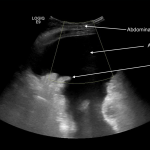

ABDOMINAL ULTRASOUND

Key features of ascites seen in this imaging modality are:

- Anechoic nature: ascites will allow sound waves to pass through it, so it will appear black/dark on ultrasound.

The gallery below organizes examples of how ascites will appear on abdominal ultrasound. Click on the thumbnails below to open up the gallery: